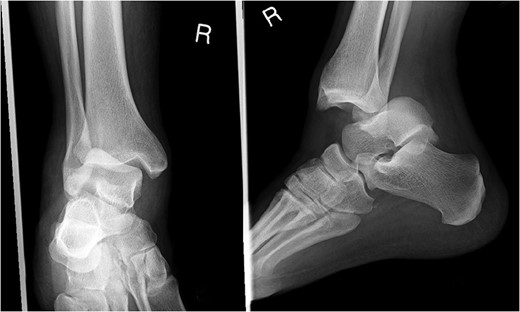

A 30-year-old male patient presented to Emergency Department (ED) following a run over injury. The patient described the mechanism of injury as moving his body over his run over foot. On clinical examination, there was obvious deformity and swelling of the right ankle. Dorsalis pedis pulse was felt but weak compared to the contralateral side with a capillary refill time under 3 s. The posterior tibial artery could not be palpated because of the deformity. X-rays showed posterior ankle dislocation without associated fractures (Fig. 1). Urgent reduction of the dislocation was done under sedation in ED. The knee was first flexed to relax the tendon Achilles then longitudinal traction with gentle forward force applied to the heel with immediate reduction of the deformity achieved. The foot was reassessed for vascular status. Triphasic pulse in both drosalis pedis and posterior tibial artery was detected with hand held Doppler. Ankle was immobilized in posterior below knee back slab to accommodate for swelling and check x-rays confirmed reduction of the ankle joint (Fig. 2). CT scan was done afterwards to define any subtle incongruity or osteochondral fragments entrapped in the joint. CT did not show any associated fractures and showed congruent reduction of the ankle joint (Fig. 3). Patient was mobilized touch weight bearing for first 2 weeks. The back slab was changed for weight bearing short leg cast and progressive weight bearing was allowed for the following 4 weeks. At 6 weeks follow up, plaster was removed and on examination patient still had moderate tenderness over the medial joint line and deltoid ligament area. Also, patient had limited range of plantar and dorsal flexion. Referral for physiotherapy was done for start of functional rehabilitation and range of motion exercises and in mean time MRI was done to delineate extent of ligamentous injury. MRI showed bone bruising of the lateral malleolus, medial malleolus and lateral talus (Fig. 4). The anterior talufibular ligament (ATFL), calcaneofibular ligament (CFL), posterior talofibular ligament (PTFL) and deltoid ligaments were sprained but intact. At 12 weeks follow up, patient could walk normally without any symptoms of instability and achieved 20° of both plantar and dorsal flexion. At 16 weeks, patient achieved full range of motion of ankle and was able to return to work. At 24 weeks follow up patient was able to resume his sport activates as preinjury level.

Plain film X-rays of right ankle showing total posterior dislocation of the ankle joint with no fracture of the medial or lateral malleolus.